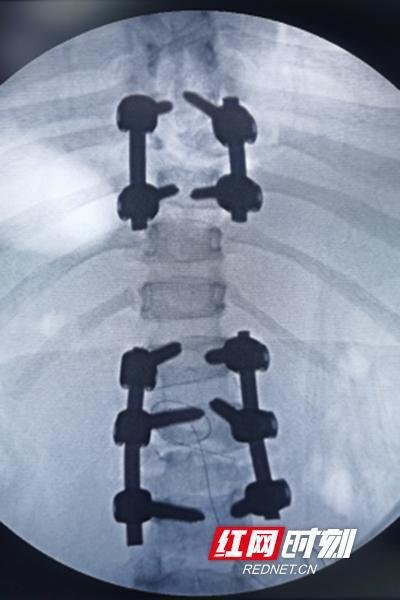

△3D打印模型

为了手术更精准,取得更好地疗效,脊柱外科团队联合该院3D打印中心技术人员,共同为该患者制定了个性化的手术方案,脊柱外科顺利为他完成了3D打印模型辅助下腰椎结核病灶清除和脊柱稳定性重建术,术后5天该患者就能佩戴支具下床活动了,仅一个星期就出院了,术后效果超乎预期。经过术后复查,该患者腰骶椎结核病灶清除干净,对植骨也很满意,脊柱内固定位置佳,稳定性好。腰疼腿麻的症状基本消失,他称赞脊柱外科让自己获得了新生。